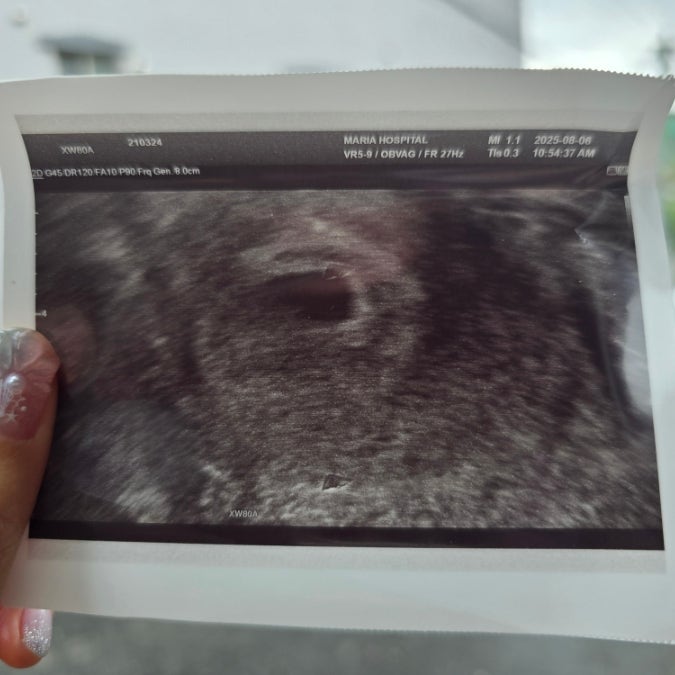

임신일기 :: 임심 7주차 난황 안보임ㅣ계류유산ㅣ소파술 후기

잇님들❣ 로지하게 입니닷 첫 임신이라 너무 기뻐 임밍아웃을 했었는데 임신 7주차에 계류유산으로 소파술...